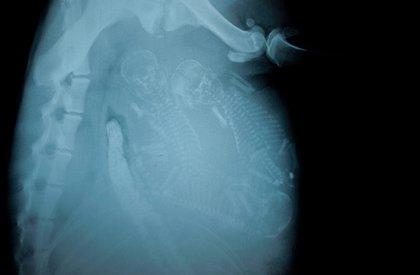

哈~這其實是動物懷孕的照片啦!美國《boredpanda》網站最近整理了一系列懷孕動物的X光照,從最常被人類飼養的貓、狗,乃至於蝙蝠、浣熊等都有,雖然小動物的誕生應該是可愛而溫馨,不過單看這些滿肚骨骸的X光照,還是覺得有點驚悚和詭異啊!

浣熊